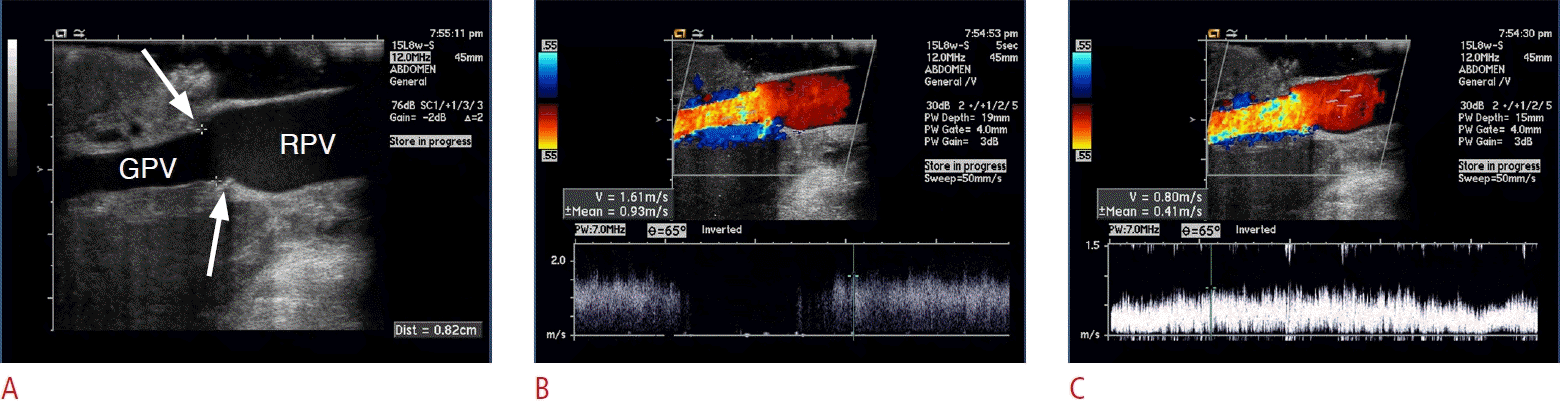

Fig. 1.

Normal grayscale intraoperative ultrasonograms of hepatic artery.

Intraoperative ultrasonogram (A) shows short linear echoes encircling the lumen (arrowheads), suggesting reverberation echo from each of anastomotic stitches. The color Doppler (B) and spectral (C) ultrasonograms show normal color flow and spectral pattern of graft hepatic artery. GHA, graft hepatic artery; RHA, right hepatic artery.

It has been shown that high-frequency (8-12-MHz) IOS, with superb resolution visualizing reverberation echo from each of anastomotic stitches, is capable of assessing the HA anastomosis as it is [3] (Fig. 1). There may be a technical difficulty in case of vascular tortuosity and small size of the vessels.

To detect HA stenosis, the diameter of HA anastomosis is first measured, followed by color and spectral Doppler US of the graft HA to identify abnormal Doppler parameters indicative of HA insufficiency, as follows: peak systolic velocity <30 cm/s, resistive index <0.5, and systolic acceleration time >0.08 seconds [3] (Fig. 2).